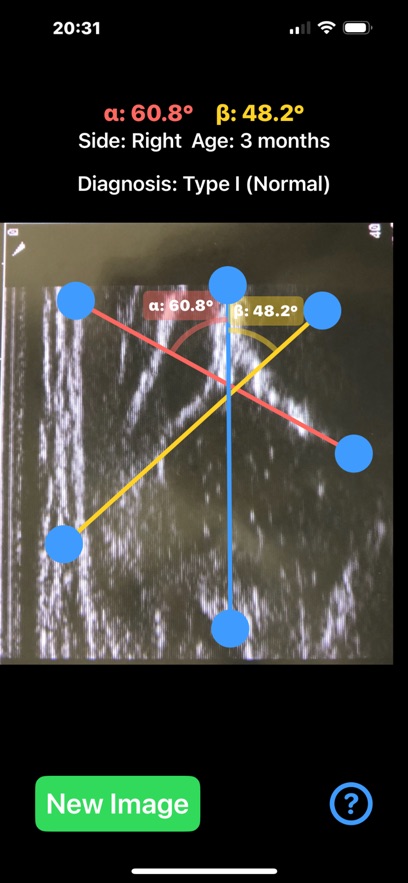

Ultrasonography, rather than X-ray, is the preferred method for diagnosing DDH in infants, especially under the age of 6 months. Ultrasound provides a non-invasive and radiation-free way to visualize the soft tissues, cartilage, and bones in real time. The Graf method is the most widely used technique, where two critical angles—alpha (α) and beta (β)—are measured to assess the development of the acetabulum and classify the hip's condition.This application is designed to aid healthcare professionals—especially radiologists, orthopaedic surgeons—in evaluating DDH by calculating the alpha (α) and beta (β) angles quickl from saved ultrasound images of the patient hip.

Provide instant visual feedback by color-coding the angles:Alpha angle (α): red, Beta angle (β): yellow. Automatically also classify the hip joint based on the Graf method Type I,Type IIa/b,Type IIc,Type III, helping clinicians to have a quick glimpse and visualise the relationship between the angles ,real time.Healthcare professionals, particularly in busy departments, can save significant time by quickly loading ultrasound images and automating angle calculations, identify abnormal hips on the go . App can also be used as a training tool for medical students, residents, and junior clinicians, teaching them how to recognise key landmarks, make accurate measurements, and classify DDH using ultrasound images. By rapid visually displaying the measurements on the screen and generating easy-to-understand images, app helps clinicians explain the condition and its severity to parents.

App offers α and β angle measurement by dragging points on the ultrasound image to key anatomical landmarks, forming lines that define the acetabular roof and cartilaginous roof. The app automatically calculates the angles and classifies the hip condition based on these measurements in real-time.

Important feedback that help allow the user to adjust draggable points and see immediate changes in the angle values helping to fine-tune the position of the lines and target the preferred anatomical landmarks of the ultrasound image more efficiently. User-friendly interface, and reliable classification system based on Graf’s classification that streamline the diagnostic process, and improved overall workflow in clinical practice.